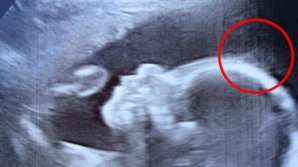

Taguri: s-a născut cu păr AU RĂMAS ŞOCAŢI când s-au uitat pe ecografie. Ce au văzut părinţii 1 ABCDEFGHIJKLMNOPQRSTUVWXYZ IMPORTANTE ALTELE